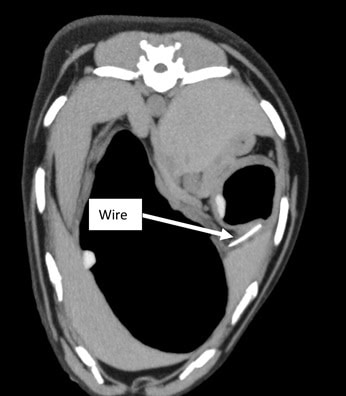

A CT image showing the wire lodged in Charlie’s stomach

On arrival, Charlie was admitted for emergency care. The team working on Charlie, led by Justine Barton RCVS Recognised Advanced Practitioner in Small Animal Medicine, initially carried out digital gastroscopy (using a camera to look inside the stomach). Strangely, no foreign material could be found. Luckily, advanced imaging (CT scanning) was also available, and this revealed the shocking cause: a piece of wire lodged within the wall of his stomach; something that has never been reported before.